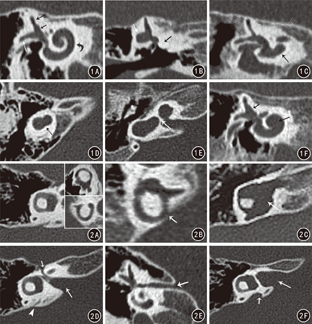

采用64层CT扫描仪(Somatom Sensation,西门子,德国)行双侧颞骨扫描,扫描时患儿取仰卧位,收拢下颌,扫描基线与听眶上线平行。扫描参数:管电压120 kV,管电流200 mAs,旋转时间1.0 s,螺距0.8,FOV 190 mm×190 mm。扫描原始数据以每侧内耳为中心,单独重建成层厚0.6 mm,层距0.3 mm,FOV 60 mm×60 mm的薄层图像,薄层图像根据文献[4]所述方法,对每侧耳的耳蜗进行斜横断位重建、各个半规管分别进行斜冠状位重建、内听道及前庭导水管进行斜横断位重建,以清楚显示内耳结构。由2名高年资医师在不知道临床诊断结果的前提下独立对68例患儿的CT原始图像及MPR图像进行观察,意见分歧时经协商后统一。

本组68例患儿共发现内耳畸形131耳(单耳畸形5例,双耳畸形63例),MPR清晰显示耳蜗畸形33耳,前庭畸形39耳,半规管畸形42耳,内听道畸形18耳,前庭导水管畸形86耳。其中8耳(6.1%,8/131)为单一结构畸形,123耳(93.9%,123/131)为2种或2种以上畸形。耳蜗畸形33耳中,21耳(63.6%)伴前庭畸形,26耳(78.8%)伴半规管畸形,7耳(21.2%)伴内听道畸形,9耳(27.2%)伴前庭导水管扩大畸形,15耳(45.5%)伴前庭及半规管畸形。正常儿童及患儿的MRP见图1、图2,具体类型见表1。双侧内耳同时畸形者63例(126耳),占92.6%(63/68),其中5例患儿两侧内耳畸形类型不一致(表2);单侧内耳畸形者5例(5耳),占7.4%(5/68)。

在胚胎发育的不同阶段内耳发育出现停滞,则会出现不同类型的耳蜗前庭畸形。内耳畸形可分为耳蜗畸形、前庭畸形、半规管畸形、内听道畸形及前庭导水管畸形,其中耳蜗畸形分为Michel畸形、共同腔畸形、耳蜗未发育畸形、耳蜗发育不良畸形、IP-Ⅰ畸形及Mondini畸形[5]。本组病例中,所有畸形中前庭导水管扩张发生率最高,耳蜗畸形中Mondini畸形发生率最高,与文献[10]报道一致,然而并未发现Michel畸形,这可能与该类畸形发生率较低有关。值得一提的是,本组病例中大部分内耳畸形并不是单一结构畸形,而是2种或2种以上内耳结构受累的多种畸形合并存在,尤其在耳蜗畸形中,较多病例伴发前庭畸形或/和半规管畸形,这提示影像学医师在日常阅片中当发现某单一结构的内耳畸形,尤其是耳蜗畸形时,一定要利用MSCT图像后处理的强大功能,注意寻找有无其它伴发畸形。本组病例中,大部分内耳畸形为双侧同时发病,且同一例患儿的双耳畸形种类大部分一致,但本研究中出现了5例同一例患儿双侧内耳畸形种类不一致的情况。由于耳蜗未发育、共同腔畸形、耳蜗发育不良及Mondini畸形的发生分别为孕3~4、4、6及7周时胚胎发育停止所致[7],这种情况的出现可能与孕妇受到某种致病因素作用后,大部分患儿的双侧内耳在短时间(约1周内)内发育受阻,而少部分患儿的双侧内耳在相对较长时间(约2~3周)内发育先后发生停滞有关,停滞时间不同而导致双侧内耳的畸形类型不同。此外,本组病例发现3例(4耳)单纯后半规管裂畸形,而Sennaroglu等[5]内耳畸形分类标准未纳入此畸形。

MPR是最常用的CT图像后处理技术之一,能够整体并准确显示正常及畸形内耳的解剖学结构,而且MPR被认为可以提高内耳畸形的检出率及诊断正确率[11]。既往报道中,对于内耳畸形的MPR诊断缺乏统一的标准,部分文献仅对内耳的结构进行了类似横断面扫描的多层显示,并未对正常及畸形内耳的结构进行全面直观的显示[12,13]。VR技术能够显示内耳畸形,尤其是耳蜗畸形的外部整体结构[14],但无法显示骨迷路内部的解剖学特点,而且较难显示前庭导水管扩大等畸形,故本研究并未采用VR技术。在本研究中,CT原始图像经统一标准进行多角度重建,清晰显示了骨迷路的正常及异常解剖结构,为临床提供了准确的影像学信息。然而,当临床怀疑前庭蜗神经缺如或发育不良时,CT扫描可能仅能显示内听道狭窄等间接影像学征象,不能显示其内的神经情况,此时有必要选择MRI来直接显示神经形态结构。此外,对于前庭导水管扩张畸形,MRI被认为具有比CT更高的检出能力[14]。